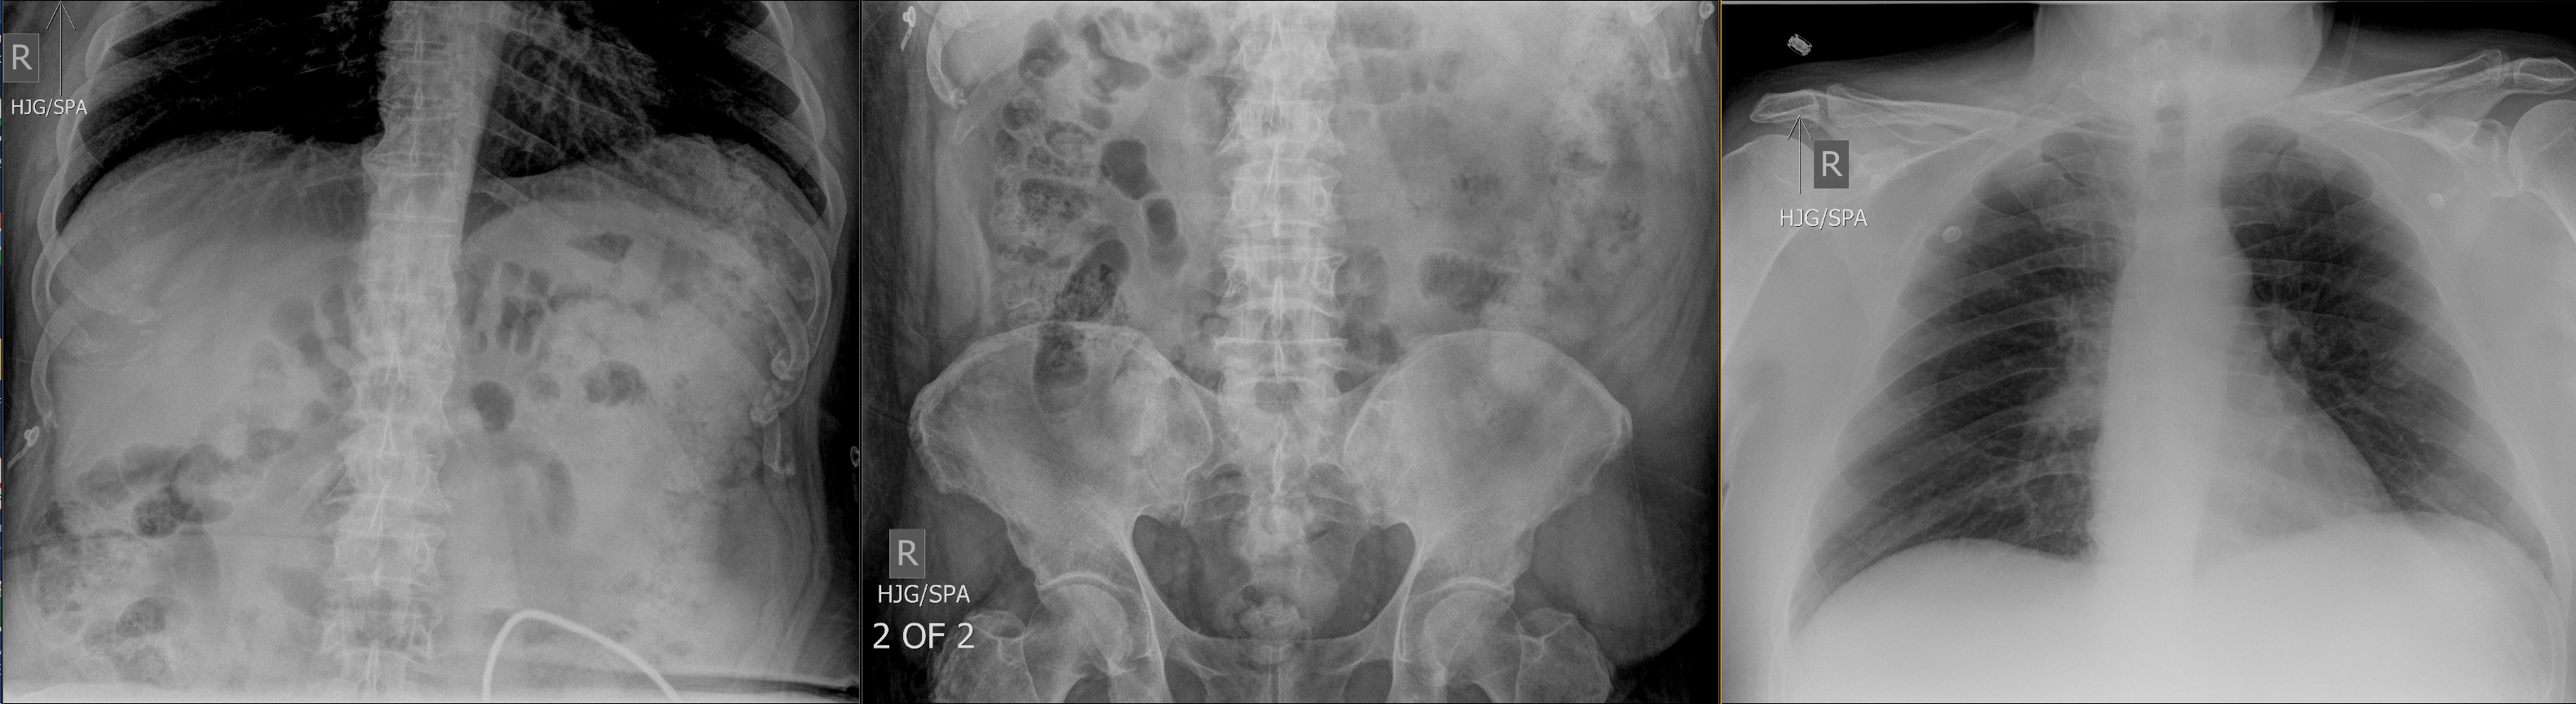

Acute abdominal series

Look at the patient's acute abdominal series. There is evidence of free air from hollow viscus perforation.

No, this patient does not have pneumoperitoneum.

View the full study if you'd like to take a look yourself.

The patient likely does not have cholecystitis. An acute abdominal series may reveal free air in the abdomen, dilated bowel, pneumatosis, portal venous gas, or be normal. A CT scan is a reasonable first step if clinical suspicion of pathology is high. For this patient, the abdominal series was initially obtained in the ED.